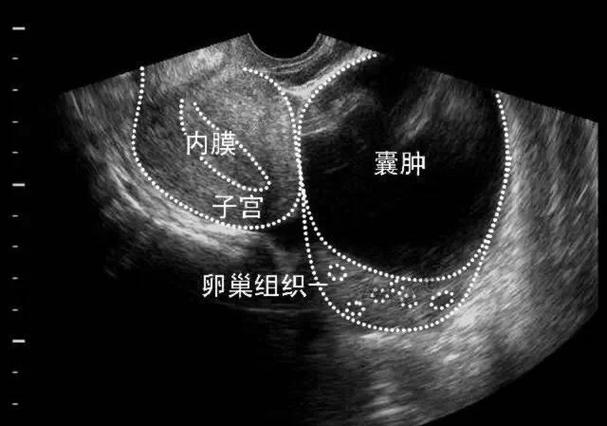

- 定期产检和监测:这是最重要的措施,医生会通过B超定期观察囊肿的大小、形态、内部回声等变化,大多数功能性囊肿会在孕中期自行缩小或消失。

- 详细检查:进行体格检查,并安排B超、血常规等检查,以确认诊断和评估腹腔内有无出血。